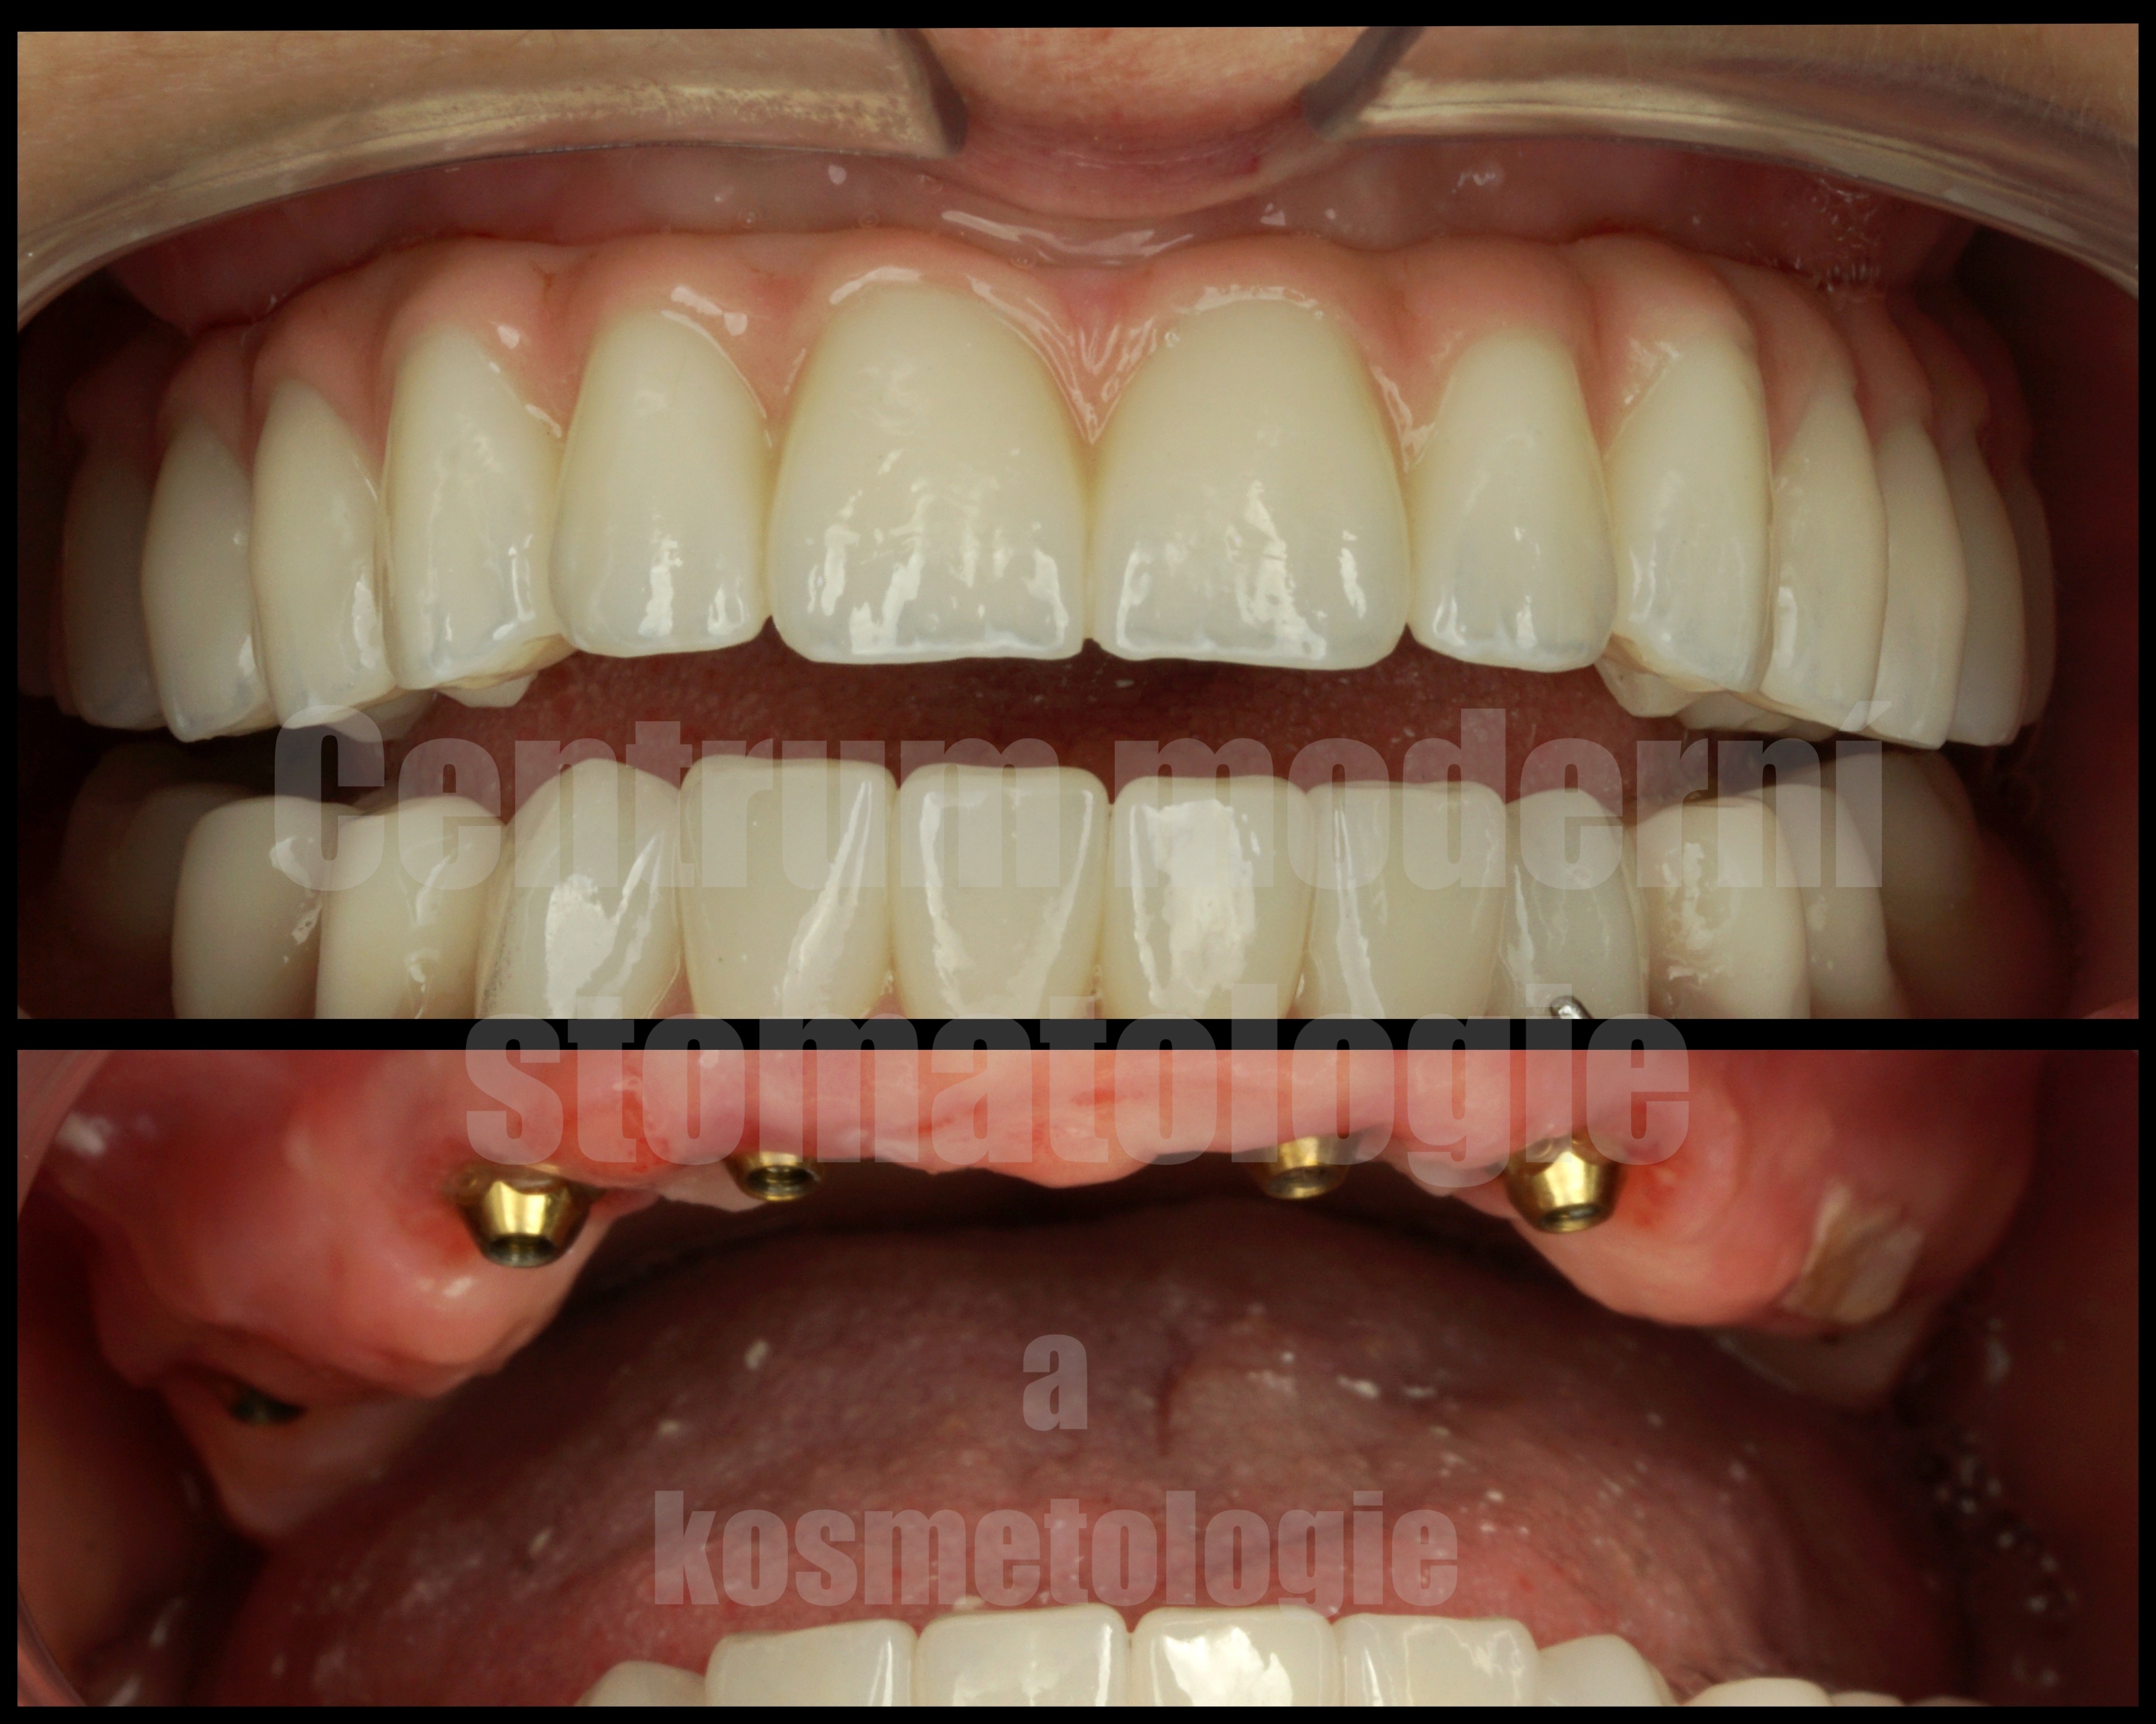

All-on-6 je moderní způsob náhrady celého zubního oblouku pomocí šesti implantátů, na kterých je upevněna fixní protetická práce.

Cílem ošetření All-on-6 je obnovit estetiku úsměvu, jistotu při kousání a komfort při každodenním fungování. Vhodnost tohoto postupu závisí na anatomii čelisti, kvalitě kosti, skusu a celkovém léčebném plánu.

Pokud jsou přítomny zuby, které již nelze dlouhodobě zachovat, může být součástí léčby jejich odstranění. Následně je podle léčebného plánu zavedeno šest implantátů, které slouží jako opora budoucí fixní náhrady.

Po implantaci následuje hojení. Za vhodných podmínek je v některých případech možné provést dočasné zatížení protetickou náhradou v krátkém čase po zákroku. Definitivní práce se zhotovuje po stabilizaci a vhojení implantátů.